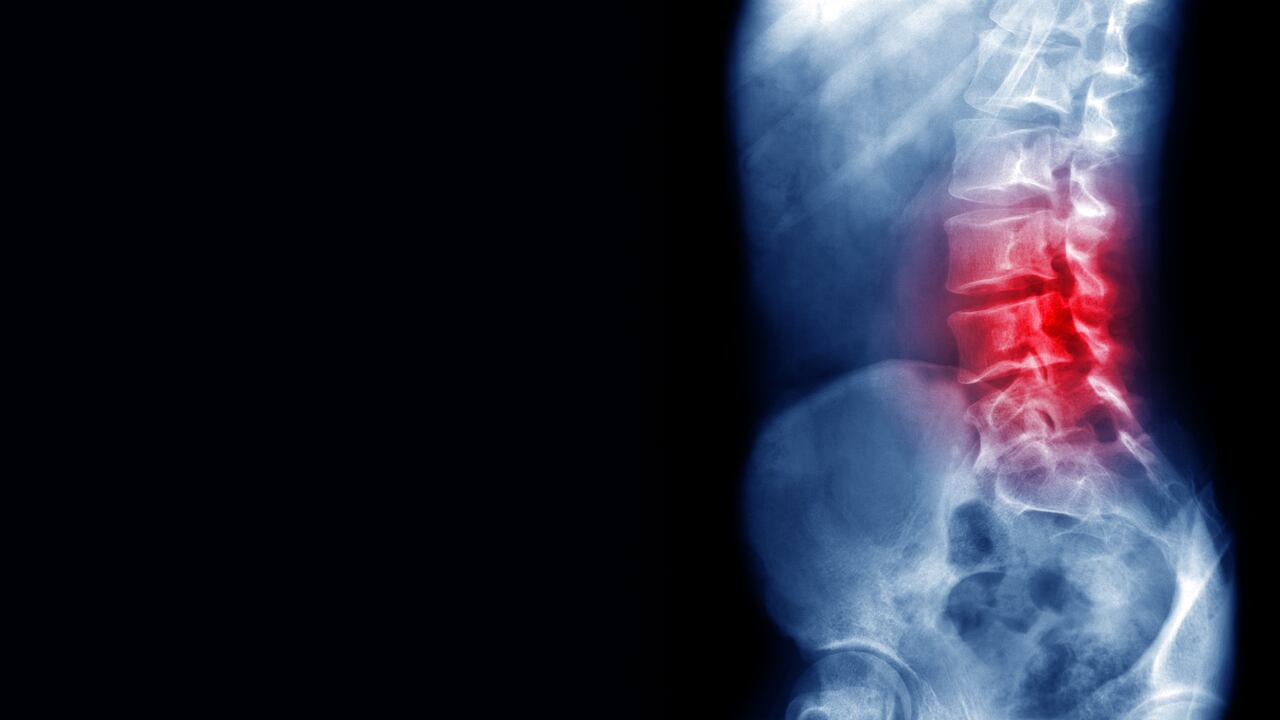

Cierra el ordenador tras un largo día de trabajo y le cuesta erguirse. Va a recoger los juguetes de sus hijos o nietos del suelo y nota cómo desciende una descarga eléctrica por su columna vertebral. Se gira en la cama y las lumbares se quejan. Si esto le ocurre de manera frecuente, y durante al menos tres meses, está claro: sufre un dolor de espalda crónico. Quizás sea buena idea entonces empezar una terapia psicológica.

El dolor de espalda (especialmente de la zona lumbar) es uno de los dolores crónicos más frecuentes. Afecta a cientos de millones de personas en todo el mundo y es uno de los motivos más comunes para acudir a urgencias.

Antes que nada se recomienda siempre descartar una causa física cuando haya dudas. Por ejemplo, una hernia discal o un pinzamiento de los nervios espinales pueden producir mucho dolor y requerir atención médica –y a veces cirugía– para aliviarlo. Una vez desestimado esto, podemos considerar al dolor crónico de espalda como primario. O en otras palabras, como una enfermedad en sí, y no la consecuencia de otra dolencia.